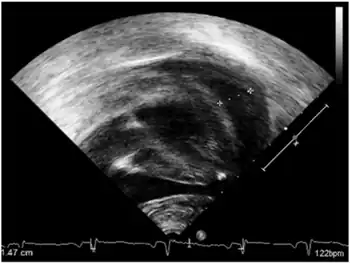

- Early onset-pericardial effusion

- heart arrhythmias

- cardiomyopathy